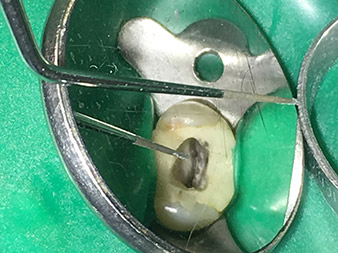

Dr. Nouraie: Yes, in my opinion. The tips allow you to work in a particularly atraumatic and minimally invasive manner. Among other steps, this applies to the exposure of the individual canal accesses, preparation of the cavity in the area of the pulp chamber, rounding off of the canal openings at the transition from the bottom of the chamber to the root canal and preparation of the coronal regions of the root canals.

It is also possible to activate the rinsing fluid in the root canal system. What’s more, it makes a range of special indications such as the revision of broken-off instruments and root posts possible.

Dr. Nouraie: I particularly enjoy working with the 1E tip. It is perfectly suited to activating the rinsing fluid in the root canal system. The delicate design of the tip allows you to reach deep sections of the canal too and ensure optimal activation.

The 4E tip – this instrument is optimally suited to preparation of the cavity floor at the transition to the canals. It can be used to round off the transition between the canal and the cavity floor optimally so as to produce a funnel leading into the canal. In addition, the instrument is the ideal choice for removing dentine overhangs from canals.

All in all, the cavity can be prepared very efficiently and minimally invasively with this tip by optimally rounding off and smoothing overhangs, corners and edges.